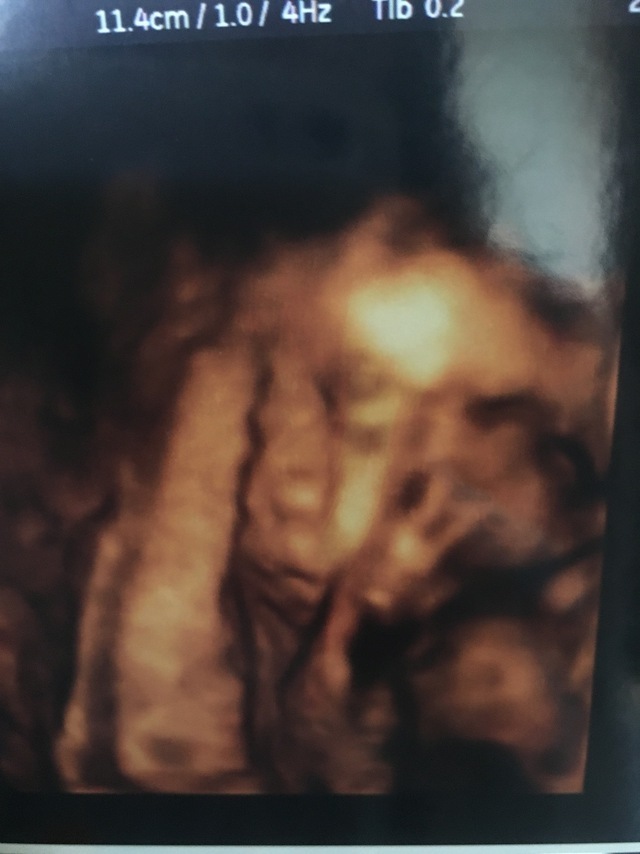

32週5日(32w5d・男の子)|おしげ さん(23歳)

エコー写真撮影時のエピソード:

妊娠9ヶ月の頃の写真です。福岡にいた私が出産のため大分に着て初めての診察で、4Dエコーするのも初めてでした。 立体的にうつる我が子をみてニヤニヤが止まりませんでした。

旦那もリアルなお腹の中の映像に感動!我が子はほっぺに手をあて、口をムニュムニュしてました。かわいいかったです。元気に生まれてきてくれた今は幸せいっぱいです。